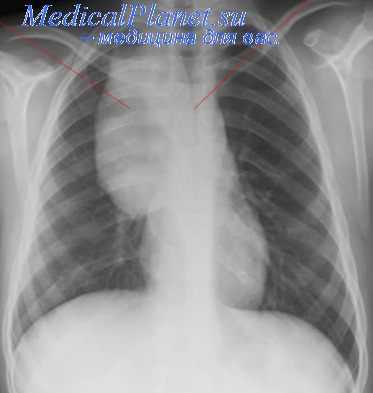

Тератомы средостения обычно располагаются в переднем средостении, рядом с крупными сосудами и перикардом. Долгое время никак не проявляются. Обычно начинают расти в подростковом возрасте или в период гестации. Могут увеличиваться до 20-25 см. Сдавливают легкие, сердце, плевру и кровеносные сосуды. Сдавление внутренних органов сопровождается учащением сердцебиения, болями в сердце, одышкой и кашлем. При прорыве тератомы средостения в бронх или плевральную полость возникает синюшность кожи, удушье, повышение температуры тела, асимметрия грудной клетки, икота, иррадиирующие боли в области надплечья на стороне поражения. Возможно легочное кровотечение и развитие аспирационной пневмонии.

Кистозные тератомы содержат в своей структуре элементы эктодермы и возникают в процессе нарушения эмбриогенеза. В медицине встречаются дермоидные кисты яичников, брюшной стенки, кожи, забрюшинной клетчатки, печени, почек и др. органов и тканей. Дермоидные кисты обычно расположены в передневерхнем отделе средостения. Величина дермоидных кист средостения может достигать 15-25 см. Форма кистозных тератом обычно неправильная овальная; консистенция эластическая или мягкая. Стенки кисты могут содержать хрящевые и известковые включения. Внутри кисты заключена густая кашицеобразная жирная масса с множеством различных включений (волос, чешуек эпидермиса, кристаллов холестерина, аморфных жиров, зубов).

Более чем в половине случаев дермоидная киста средостения сопровождается различными сердечно-сосудистыми нарушениями: приступами стенокардии, болью в области сердца, тахикардией. У 30% больных признаком дермоидной кисты средостения служит появление продуктивного кашля с выделением кашицеобразной массы, содержащей примесь волос и жира, что наблюдается при прорыве кисты в бронх. У части пациентов отмечается выпячивание грудной стенки в проекции расположения опухоли.